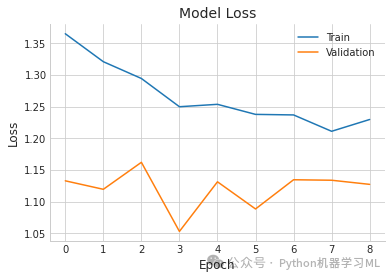

plt.plot(history.history['loss'], label='Train') # 绘制训练集损失曲线

plt.plot(history.history['val_loss'], label='Validation') # 绘制验证集损失曲线

plt.title('Model Loss') # 设置图表标题

plt.ylabel('Loss') # 设置y轴标签

plt.xlabel('Epoch') # 设置x轴标签

plt.legend() # 显示图例

plt.show() # 显示图表